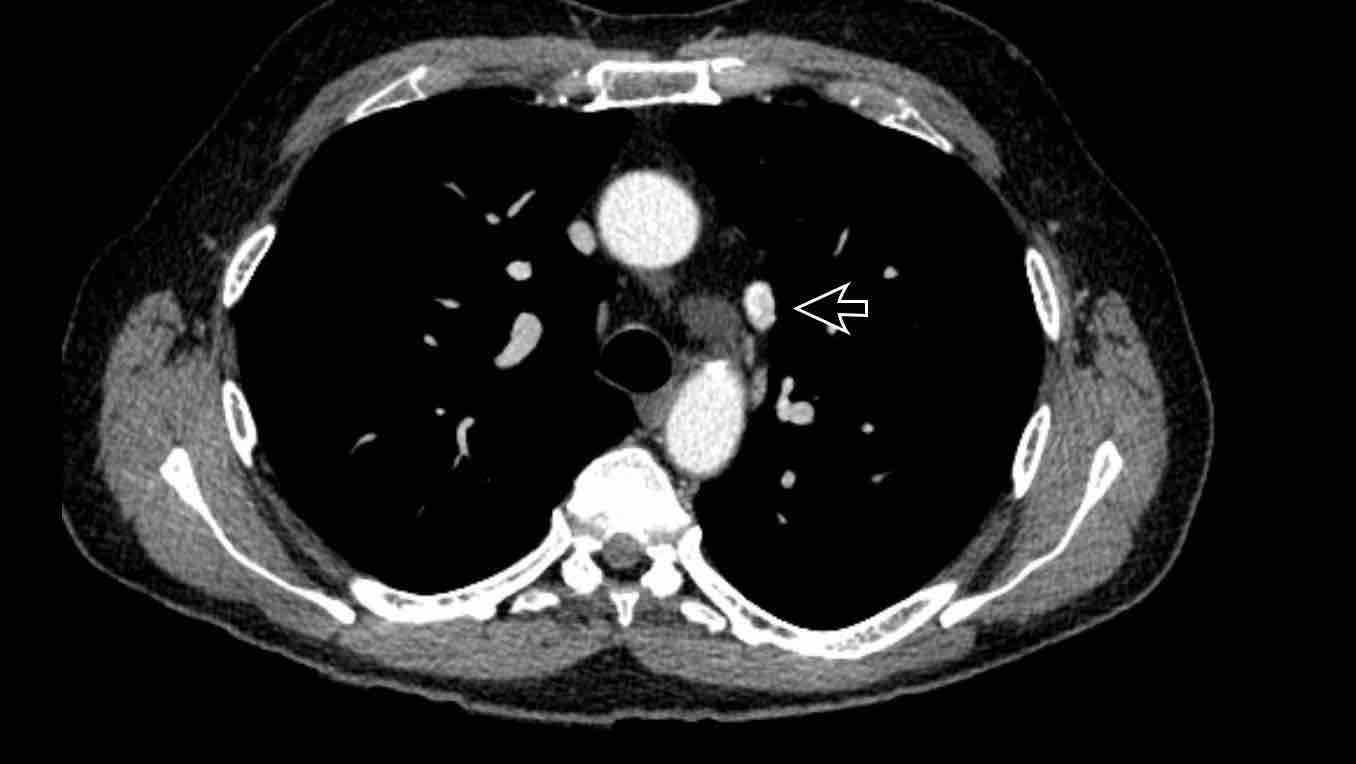

Hình ảnh

Bệnh nhân này được lên kế hoạch cắt thùy trên phải do ung thư phổi và bất thường mạch máu này ban đầu đã bị bỏ sót trên hình ảnh CT.

Những hệ quả trong phẫu thuật của bất thường như vậy nhấn mạnh tầm quan trọng của việc không bỏ sót các biến thể này.

Cuộn qua các hình ảnh.

PAPVR bên trái phát hiện tình cờ với dẫn lưu trên tim của máu từ thùy trên trái vào tĩnh mạch tay đầu trái (các mũi tên).